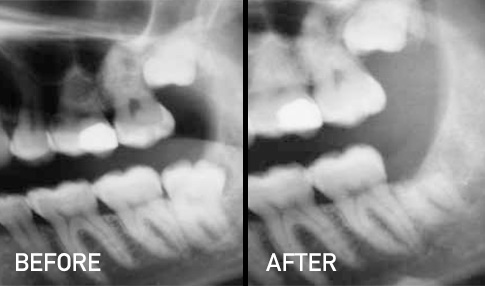

A coronectomy involves removing only the top part (crown) of the wisdom tooth while leaving the roots in place. This method is carefully considered when the roots are positioned close to the inferior alveolar nerve (IAN)—a major nerve running through the jawbone.

- Lower Risk of Nerve Damage

By avoiding the roots, we minimize the chance of injuring the IAN during removal. - Conservative Approach